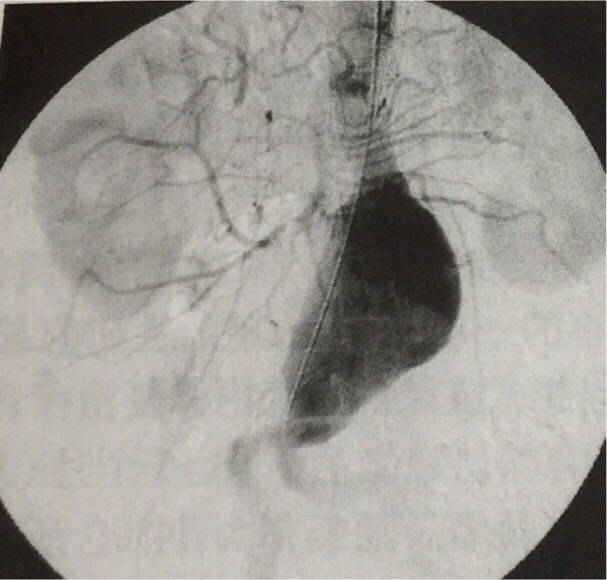

老年男性,既往有冠心病史,左心室射血分数40%,高血压病史,因触及腹部搏动性肿物就诊,造影见巨大肾动脉下腹主动脉瘤,直径8.5cm,图二为介入治疗后,未见血液内溢漏征象。对于直径大于5.5cm的腹主动脉瘤,尽早处理!